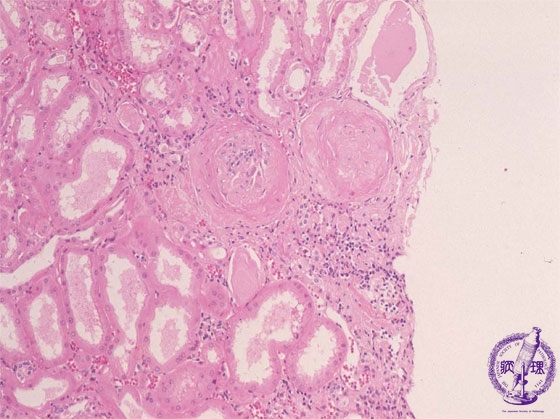

- 12.Kidney and Urinary System

- ★(10)Nephrosclerosis(benign nephrosclerosis)

Microscopic findings (HE, middle power view): The wedge-shaped compressed region (blue dotted line) shows sclerosis of the glomeruli (yellow dotted lines) and atrophy of the tubules (green dotted lines).